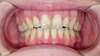

Cas 2 : syndrome du fil sur une canine mandibulaire et deux incisives mandibulaires